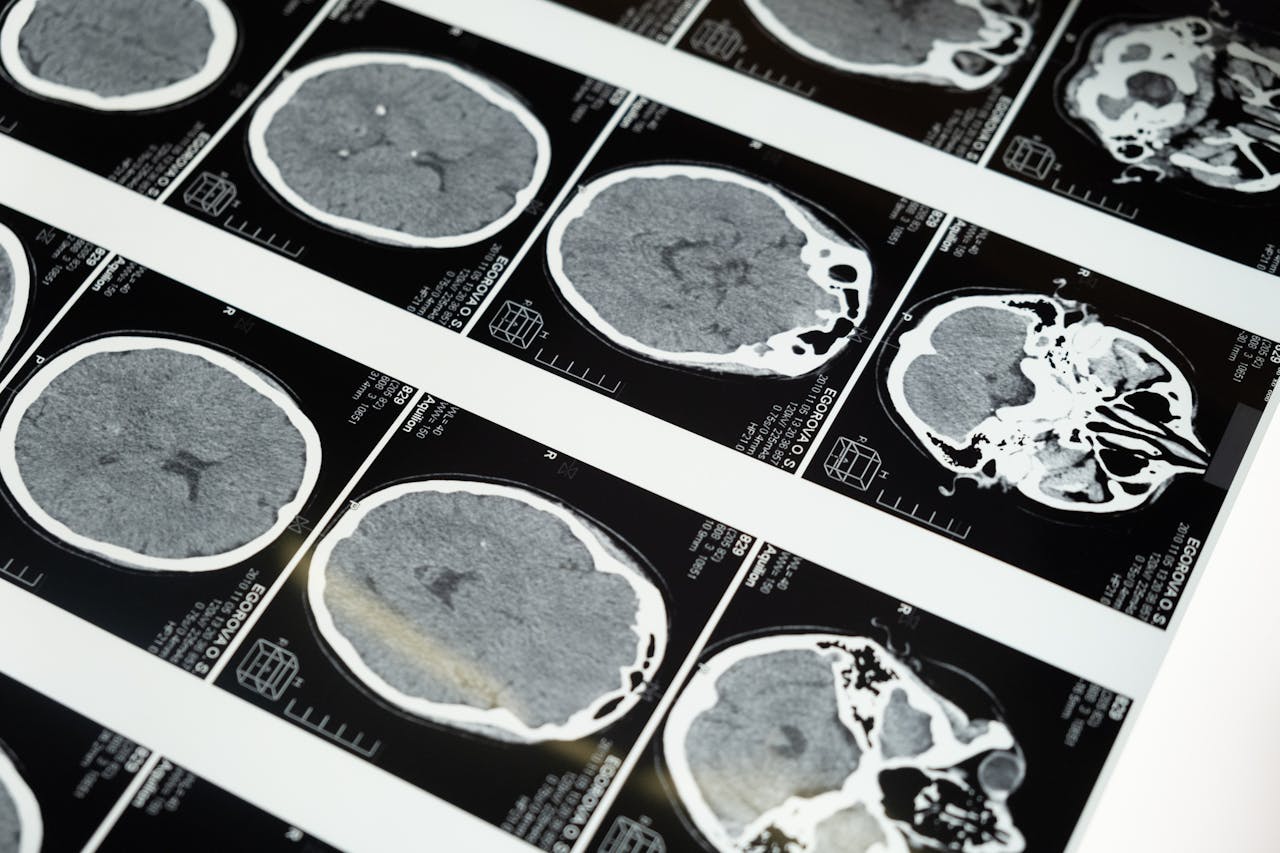

Duecento quesiti clinici sono stati proposti a diversi modelli di intelligenza artificiale, spaziando dalle patologie ematologiche alle neoplasie più complesse. Il verdetto è stato secco: il 70% delle risposte conteneva almeno un errore clinico, mentre il 30% presentava riferimenti bibliografici inventati, privi di qualsiasi riscontro scientifico. E non si trattava di sfumature: in più casi l’algoritmo ha confuso carcinomi distinti o descritto tumori mai diagnosticati. La lucidità dell’esposizione ha reso più insidioso l’errore, mascherandolo sotto una coltre di apparente autorevolezza.

Un team di ricercatori ha progettato cinque scenari simulati, modellati su reali casi diagnostici. Ogni quadro clinico è stato costruito seguendo le linee guida più recenti e approvato da specialisti esperti. Lo scopo era sondare il margine d’affidabilità di un chatbot messo nelle condizioni di operare come assistente decisionale. Solo il 32% delle risposte si è rivelato privo di errori significativi. Il resto del campione ha esibito diagnosi scorrette, interpretazioni fuorvianti e un uso disinvolto di fonti inattendibili.

Un secondo studio, condotto in una struttura ospedaliera milanese, ha esteso la sperimentazione all’ambito neurologico. ChatGPT e Gemini sono stati messi alla prova durante prime visite neurologiche su 28 pazienti veri. I medici in carne ed ossa hanno centrato la diagnosi nel 75% dei casi. L’intelligenza artificiale, invece, si è fermata al 54% e al 46% rispettivamente. Oltre alle incertezze diagnostiche, i due modelli tendevano a raccomandare un numero spropositato di esami, con una media che oscillava tra il 17% e il 25%, alimentando un rischio di iper-medicalizzazione.